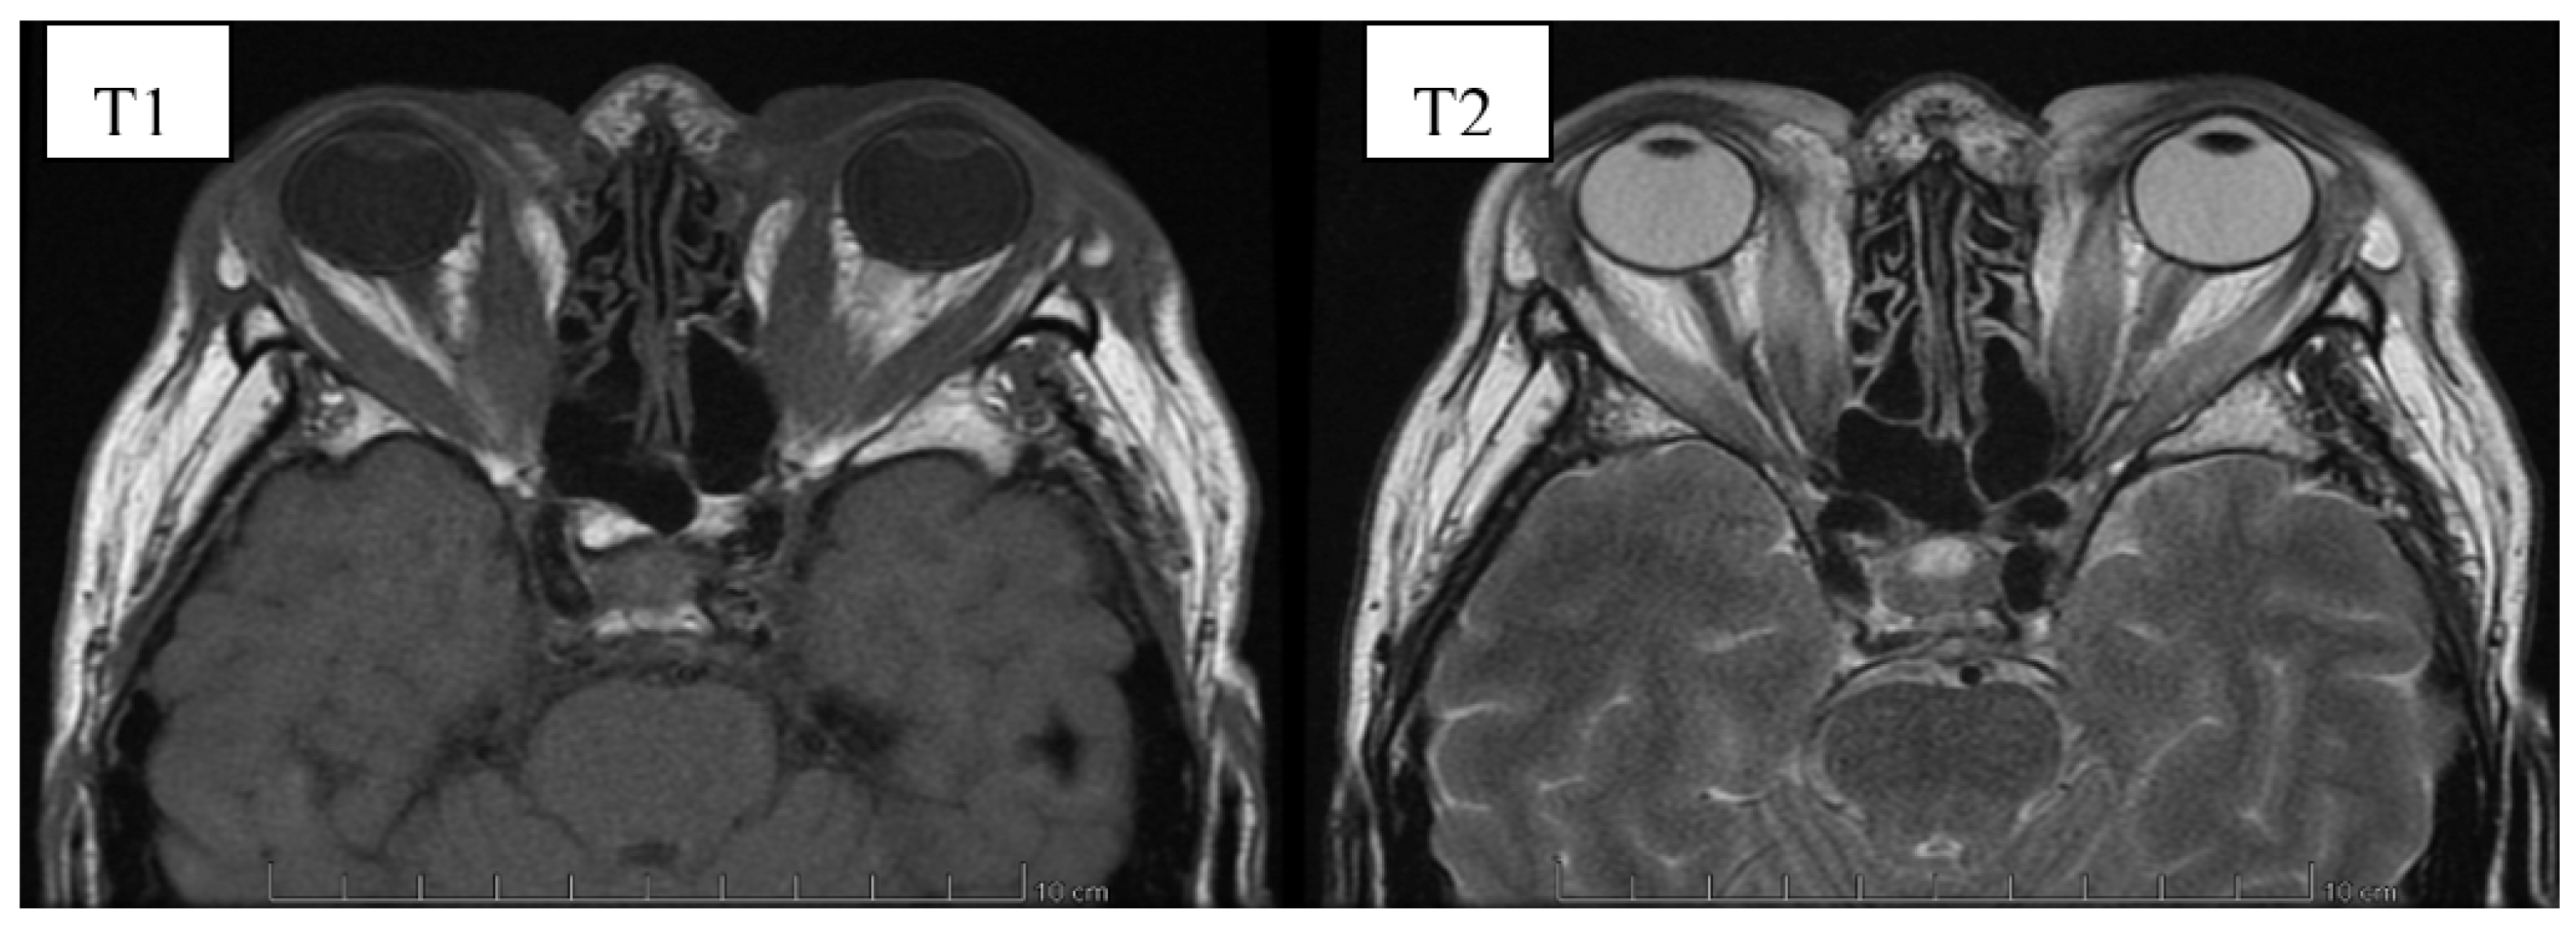

6. Image Evaluation

- Gonçalves, A.C.P.; Gebrim, E.M.M.S.; Monteiro, M.L.R. Imaging studies for diagnosing Graves’ orbitopathy and dysthyroid optic neuropathy. Clinics 2012, 67, 1327–1334. [Google Scholar] [CrossRef]

- Kahaly, G.J. Imaging in thyroid-associated orbitopathy. Eur. J. Endocrinol. 2001, 145, 107–118. [Google Scholar] [CrossRef]

- Müller-Forell, W.; Kahaly, G.J. Neuroimaging of Graves’ orbitopathy. Best Pract. Res. Clin. Endocrinol. Metab. 2012, 26, 259–271. [Google Scholar] [CrossRef] [PubMed]

- Cakirer, S.; Cakirer, D.; Basak, M.; Durmaz, S.; Altuntas, Y.; Yigit, U. Evaluation of extraocular muscles in the edematous phase of Graves ophthalmopathy on contrast-enhanced fat-suppressed magnetic resonance imaging. J. Comput. Assist. Tomogr. 2004, 28, 80–86. [Google Scholar] [CrossRef]